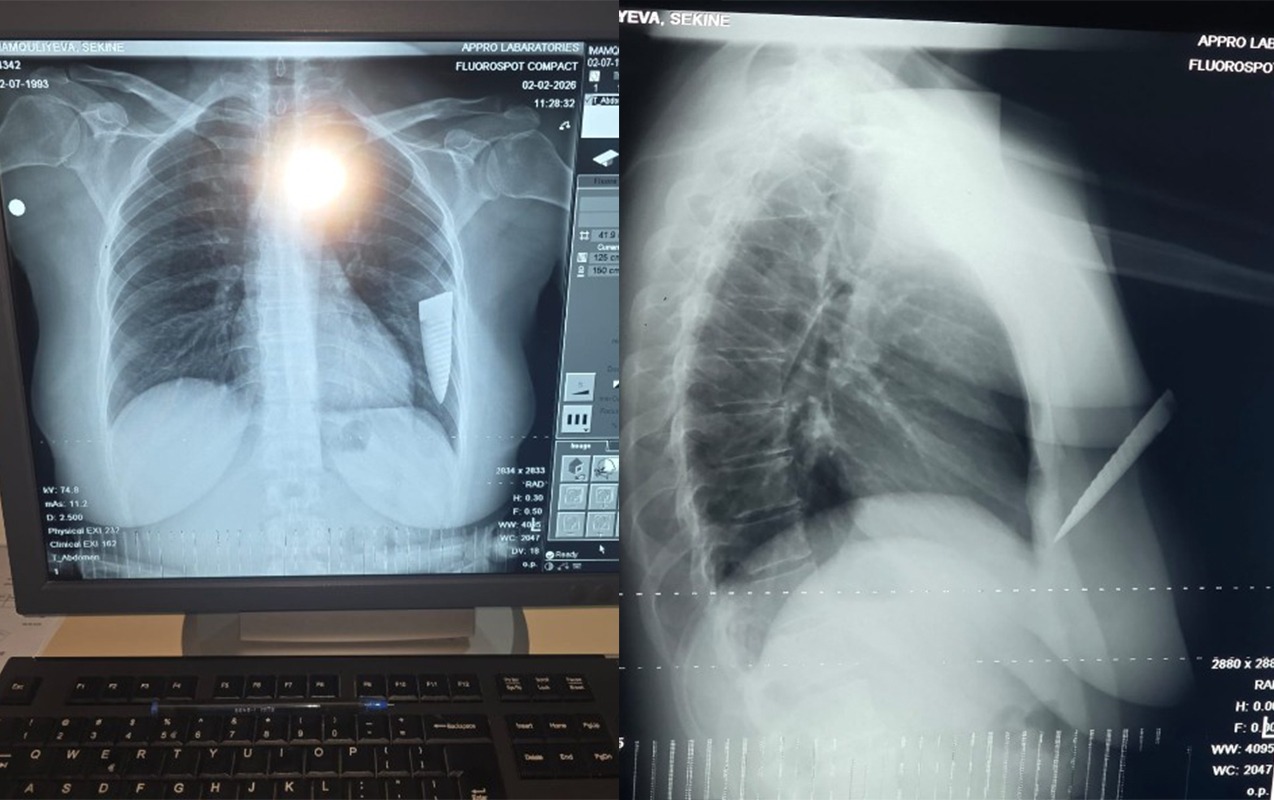

“Hadisə fevralın 1-də saat 19:00 radələrində yaşadığım Gəncə şəhərindən Şəmkirə dəvət edildiyim toy mərasimindən çıxarkən baş verdi. Şadlıq evinin qarşısında maşınıma minərkən əvvəllər qeyri-rəsmi münasibətdə yaşadığım Əli Kamran oğlu Əsgərov qəfil hücum etdi. O, gözlənilmədən maşınıma yaxınlaşdı, sağ ön qapını açaraq boğazımdan tutub boğmağa çalışdı. Daha sonra cibindən bıçaq çıxarıb 4 dəfə zərbə endirdi. Zərbələrdən biri ürək nahiyəmə, üçü isə sol qoluma dəydi. Həmin vaxt bıçaq qırılaraq döş qəfəsimdə qaldı, yoxsa daha çox zərbə endirib məni öldürə də bilərdi, çünki bıçaqla ardıcıl olaraq məni vururdu. Bıçağın qırıldığını, ətrafdakı insanların səs-küyə gəldiyini görərək qaçıb getdi”, - şikayətçi bildirib.

S.İmamquliyeva qeyd edib ki, hadisəyə səbəb onun sevgilisindən ayrılması olub: “Artıq münasibətimiz bitmişdi. Əli Əsgərov ayrılıqdan sonra məni mütəmadi izləyir, hədə-qorxu gəlirdi. Məni bıçaqlayandan sonra Şəmkir Rayon Mərkəzi Xəstəxanasına, oradan isə Gəncə Beynəlxalq Xəstəxanasına aparılaraq əməliyyat olundum. Döş qəfəsimdə qırılıb qalan bıçağın kəsici hissəsi əməliyyatla bədənimdən xaric edildi. Hazırda səhhətimdə yaranmış ağır fəsadlar səbəbindən işləyə bilmirəm. Bu hadisəyə görə külli miqdarda maddi-mənəvi zərərlə üzləşmişəm, qarşı tərəf isə heç maraqlanmır. Hadisəni törədən şəxsin saxlanıldığı bildirilsə də, istintaqın gedişindən də məlumatsızam. Qarşı tərəf imkanlıdır və təsir imkanları çoxdur. Həyatıma hər an təhlükə ola bilər. Bu işin ədalətli araşdırılmasını və təhlükəsizliyimin təmin olunmasını istəyirəm”.